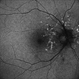

- Angioid Streaks

- 50 YEAR OLD FEMALE WITH NO SYSTEMIC ILLNESS WITH A CLASSICAL PICTURE. VISION REMAINS 6/6. THE FELLOW EYE HAS A SUBFOVEAL SCARRED CHOROIDLA NEOVASCULAR MEMBRANE.